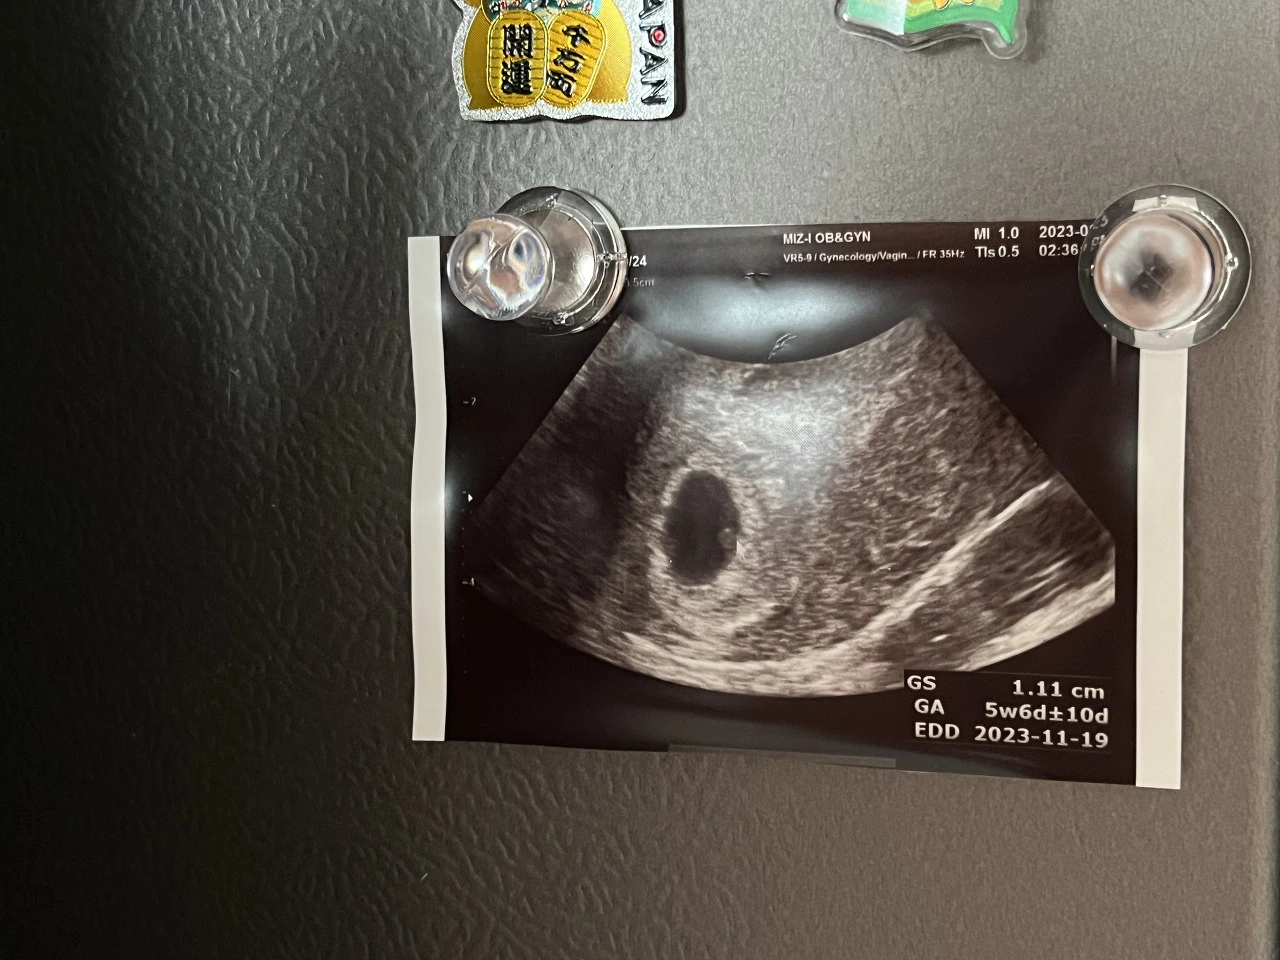

테스트기를 한 날은 주말이였기에 다음날인 일요일에 한번 더 해보고 또 그 다음날 남편이 휴가를 내 함께 내원했다. 병원에 가면 우선 피를 뽑고 의사와 상담을 한다. 병원에 간 날은 딱 생리날이 였는데 그날 간다고 하더라도 초음파나 임신확신, 아기집은 볼 수 없다. 99%의 임신사실을 확인하고 다음주에 오라는 말을 듣게 된다. 익히 드라마에서 입덧과 함께 테스트기두줄, 그리고 병원에서 “축하합니다 임신입니다!” 를 외쳐주는 곳이... 있을까? 싶다. 약간은 찜찜한 임신사실을 확인하고 나서부터 나는 불안에 떨었다. 다음주에 갔는데 임신이 아니면 어쩌지? 하는 쇠똥구리의 똥같은 생각이 들었다. 물론 그똥은 일주일 내내 잘 자라서 나를 깔아 뭉게 일주일동안 멕아리없이 한짐을 싣고 다녀 가라앉은 트럭같았다. 드디어 병원가는 날이다. 기다리고 기다리던 병원에 간다. 접수를 하고 한참을 기다려 드디어 질초음파를 했다. 아직 배위로 하는 초음파는 아기집이 작아서 보이지 않기 때문에 라고 했다. 드디어 보인다 나의 아기의 집. 동그란 집을 보니 나도 모르게 차오르는 눈물이 앞을 가렸다.